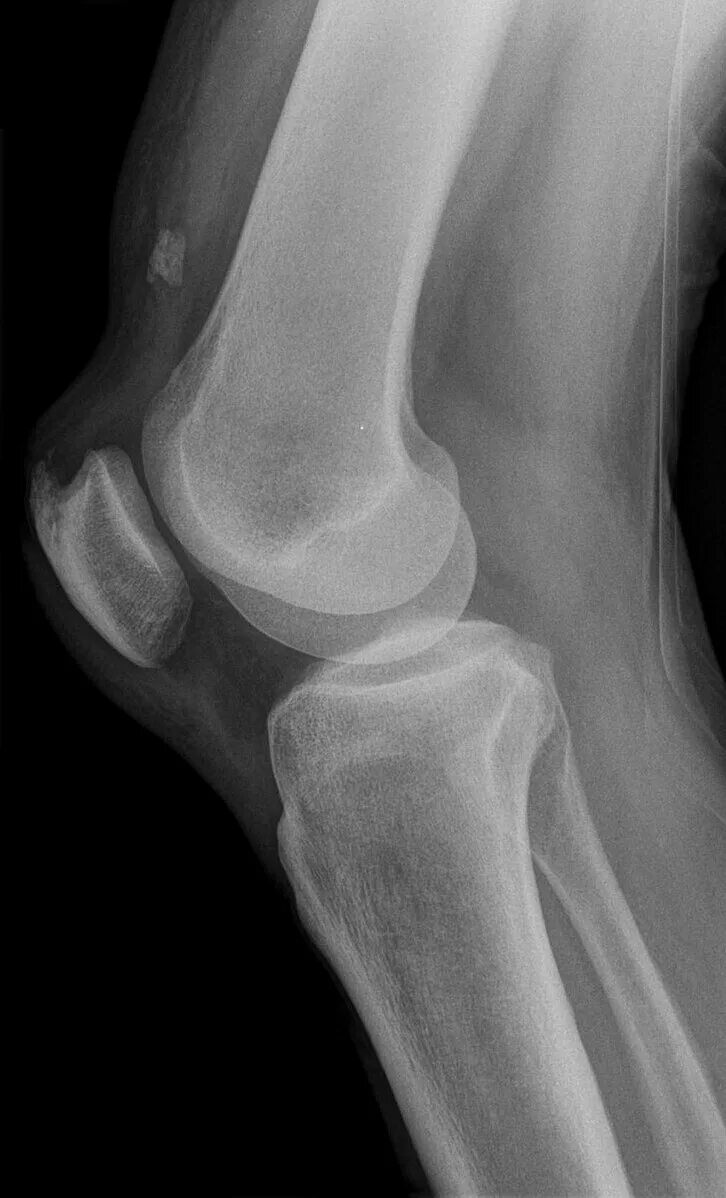

Обызвествление места прикрепления сухожилий